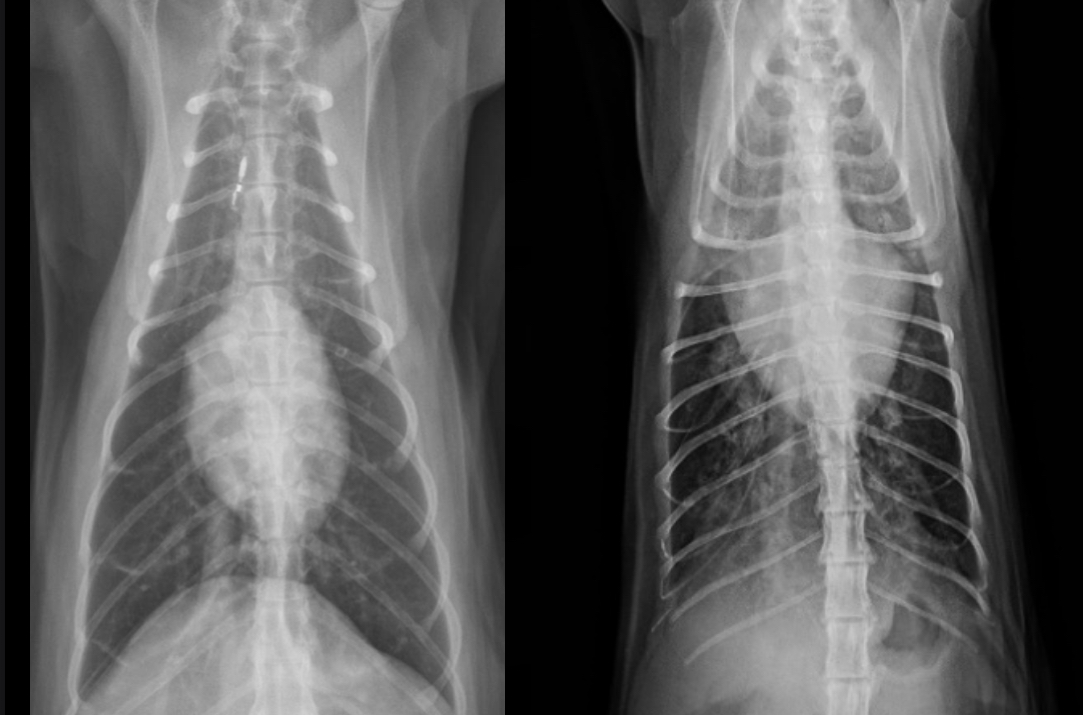

Features of generalized cardiomegaly in dogs and what disease is associated with this?

-combo roentgen signs involving L and R cardiac chambers

-dogs often get mitral dz which results in both L+R heart enlargement

-tall + wide, sternal contact

what part of the heart is enlarged in this dog

Generalized (whole thing)

Generalized cardiomegaly in cats features and what disease associated with this

-change in shape = abnormal (hard to tell what chamber affected tho) —> results in valentine shape

-HCM —> big LA and L. Au —> probably baggy left atrium that makes the whole thing look “huge”

What part of the heart is enlarged in this cat

Generalized (the whole thing)